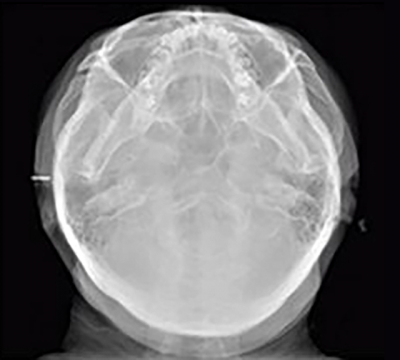

CAN CEPHALOMETRIC

(ONE SHOT TYPE)

PaX-i OPG

The PaX-i provides optimal images exclusively designed for orthodontics.

There are two image sizes available, Lateral and Full Lateral, allowing you to choose your image size based on your diagnostic needs.

PA

PaX-i OPG

CAN CEPCEPHALOMETRIC

(ONE SHOT TYPE)

The PaX-i provides optimal images exclusively designed for orthodontics.

There are two image sizes available, Lateral and Full Lateral, allowing you to choose your image size based on your diagnostic needs.

PA